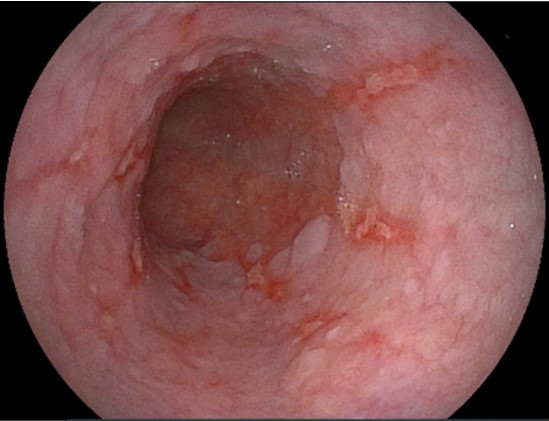

食道カンジダ症

カンジダは真菌(カビ)であり、常在菌です。通常は、感染することはありませんが免疫力が低下していると感染を起こし増殖します。そのため、糖尿病などの既往症がある場合や別の疾患でステロイド治療を受けている場合にはリスクが高いと言えます。感染して増殖すると食道粘膜で白い苔(こけ)のように広がり、胃カメラ検査で簡単に発見できます。つかえやしみる感じといった自覚症状はないこともあります。自然治癒が期待できる場合は経過観察し、症状がある場合には抗真菌薬の内服による治療をおすすめしています。

カンジダは真菌(カビ)であり、常在菌です。通常は、感染することはありませんが免疫力が低下していると感染を起こし増殖します。そのため、糖尿病などの既往症がある場合や別の疾患でステロイド治療を受けている場合にはリスクが高いと言えます。感染して増殖すると食道粘膜で白い苔(こけ)のように広がり、胃カメラ検査で簡単に発見できます。つかえやしみる感じといった自覚症状はないこともあります。自然治癒が期待できる場合は経過観察し、症状がある場合には抗真菌薬の内服による治療をおすすめしています。